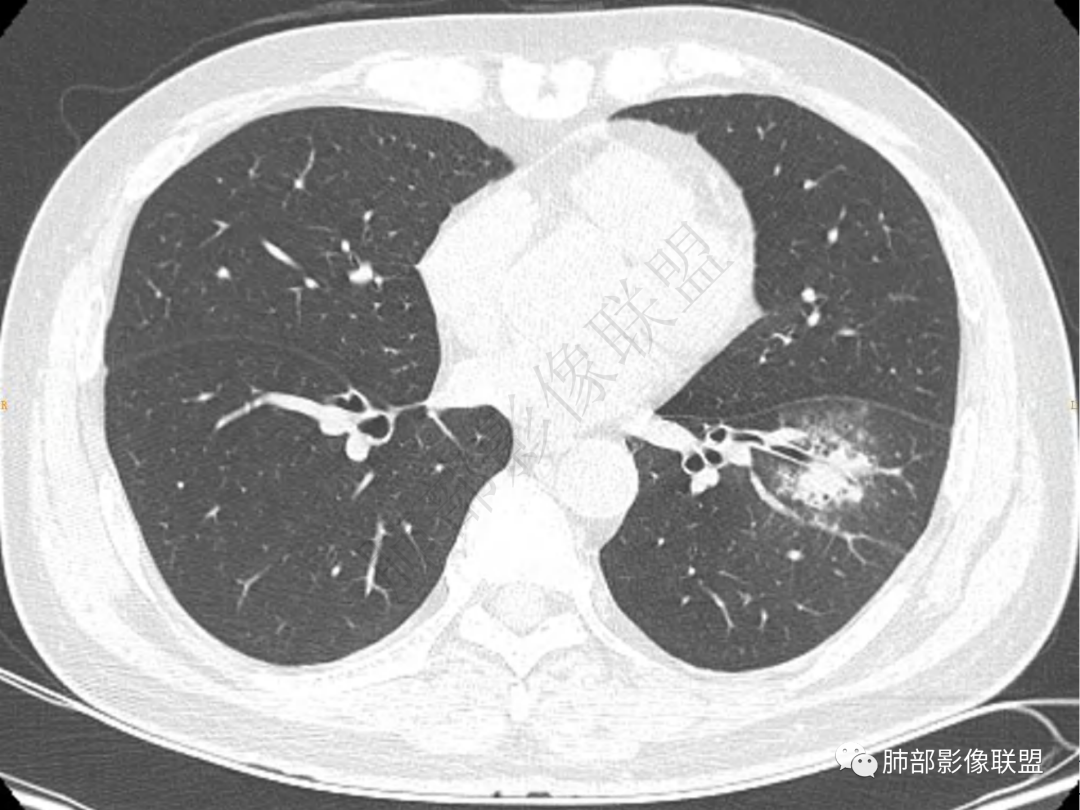

1.中年男性,咳嗽咳痰20余天,间断咯血2周

2.左肺下叶团片影,跨背段及内前基底段,实性部分类椭圆形,密度不甚均匀,可见毛刺及棘状突起,未见典型分叶及胸膜凹陷。病灶上下缘可见相应肺段支气管旁进侧出,管壁轻度增厚,未见狭窄阻塞。

3.周边较大范围磨玻璃影,边界相当模糊,小叶增厚明显。注意叶裂另一侧、左肺舌段亦可见磨玻璃影及增厚的小叶间隔。未见明确卫星病灶。

4.实性部分不均匀环形强化并显示一小范围低密度坏死区或空洞。较之肺窗,整体纵隔窗范围较小,提示病灶并不十分密实。抑或为不同时段图像。

5.双肺门及纵隔未见增大淋巴结。未见胸腔积液。

1.病灶不够密实,没有典型分叶,收缩乏力等,支气管未见截断等,缺乏一般肿瘤性肿块特征。

2.周围磨玻璃影边界不清缺乏限制,甚至“激惹”到相邻肺叶,也许提示较明显的炎性水肿。

正如多数老师分析到的,本例病灶炎性特点比较明显。